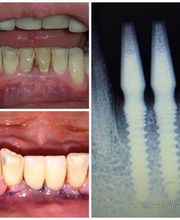

Galleria

Gallery Cliente